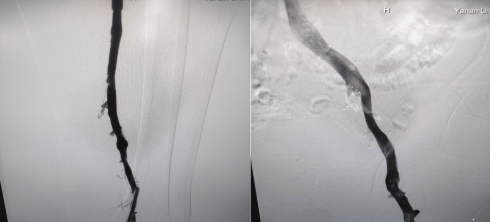

術(shù)中造影左下肢股靜脈、腘靜脈大量血栓形成